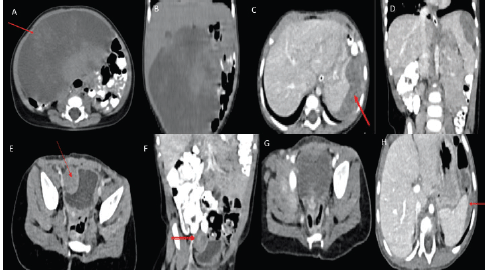

A 3-month-old female with an uncomplicated childbirth presented with a gradually progressive abdominal distension without any change in bowel habit or constitutional symptoms. Contrast-enhanced computed tomography (CECT) scan of chest, abdomen and pelvis showed a large ill-defined homogenous hypodense lesion of size 8.4 × 11.4 × 11.3 cm (APxTRAxSag), predominantly on the right side of the abdomen and in the midline showing mild heterogeneous post-contrast enhancement on delayed images (at 5 minutes) (Figure 1a and b). These findings were suggestive of a mesenteric mass, likely malignant. She underwent exploratory laparotomy with gross total excision of the mass and resection anastomosis of the involved small bowel. Histopathology showed a spindle cell tumour with cells arranged in a fascicular and haphazard pattern with abundant admixture of inflammatory cells rich in plasma cells, lymphocytes and few oeosinophils. The tumour cells showed mild-to-moderate pleomorphism with finely dispersed chromatin and moderate-to-abundant oeosinophilic cytoplasm. Variable mitosis was seen (4–5/10 per high-power field) (Figure 2a and b). Tumour cells showed diffuse nuclear immunoreactivity for ALK-1 protein (100%) on D5F3 Ventana platform and cytoplasmic positivity for smooth muscle actin (SMA) and desmin (Figure 2c and d). Hence, a diagnosis of infantile IMT was suggested. She developed abdominal pain 6 months after surgery and imaging (CECT) showed recurrent disease in right paravesical and left subdiaphragmatic regions (Figure 1e and f). As resection would have required debilitating surgery in the form of splenectomy and partial cystectomy, she was started on ceritinib 150 mg once a day (300 mg/m2) with food (the child was able to swallow the capsule), after discussion with the multidisciplinary tumour board. The child was monitored for toxicity with two weekly complete blood counts, liver and renal function tests for the first month, followed by monthly liver function testing. An electrocardiogram (ECG) was obtained prior to starting ceritinib, at 2 weeks of starting treatment and then monthly. Response assessment after 2 months showed a near-complete response with the disappearance of the paravesical lesion and 95% reduction of the subdiaphragmatic lesion (Figure 1g and h). A follow-up scan at 6 months of starting ceritinib showed complete response to therapy with no toxicity.

Figure 1. (a, b): Pre-operative CECT abdomen axial coronal images showing a large hypodense mesenteric lesion with mild heterogeneous post-contrast enhancement displacing small bowel loops to the left side and ascending colon posteriorly and abutting inferior surface of liver with no obvious infiltration. (c, d): CECT abdomen at recurrence axial coronal images showing a heterogeneously enhancing lesion in the left subdiaphragmatic region abutting the superior surface of the spleen with indentation and loss of fat plane. (e, f): CECT abdomen axial coronal images showing a heterogeneously enhancing lesion in the right paravesical region indenting the right lateral wall of urinary bladder with loss of fat plane. (g, h): Two months post-Ceritinib CECT abdomen axial images showing complete resolution of a right paravesical lesion and near-complete resolution of the left subdiaphragmatic lesion.